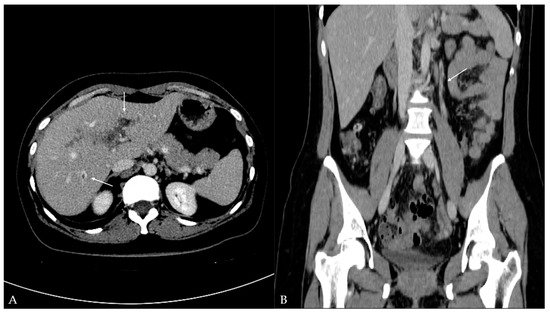

Twelve days later, the patient presented to the ED with a two-day fever (38 °C) and no other symptoms. The postoperative scar and ileostomy were unremarkable, and no signs of peritonitis were detected on clinical examination. Laboratory blood tests showed leukocytosis [15.56 (3.4–9.7 × 109/L)] with neutrophil predomination [10.99 (2.06–6.49 × 109/L)] and elevated liver enzyme [AST 63 (11–34 U/L), ALT 153 (8–41 U/L), GGT 220 (9–35 U/L), ALP 185 (54–119 U/L)] and CRP levels [99.6 (<5 mg/L)]. Other parameters were within the normal values. The attending surgeon referred the patient to the transabdominal US under suspicion of fluid collection. The US and color Doppler (CD) analysis showed left portal vein thrombosis and preserved patency of the hepatic arteries, veins, and inferior vena cava (Figure 1). No free fluid or collection was found. The patient was then referred to contrast-enhanced abdominal and pelvic CT to evaluate the extent of the thrombosis (Figure 2). The left branch of the portal vein was occluded entirely, and the segmental branch of the right portal vein was partially occluded. Thrombotic content was also found in the inferior mesenteric vein. No free fluid, collection, or liver and bowel perfusion abnormalities were found. Due to the described findings and recent diverticulitis, pylephlebitis was the imaging diagnosis. The patient was admitted to the hospital and put on low-molecular-weight heparin (LMWH) and intravenous administration of antibiotics (meropenem).

Figure 2.

Contrast-enhanced computed tomography of the abdomen and pelvis: (A) axial plane—hypodense filling defects (thrombus) in the left portal vein and additionally in the segmental branch of the right portal vein (arrow); (B) coronal plane—additional hypodense filling defects (thrombus) detected in the inferior mesenteric vein (arrow).